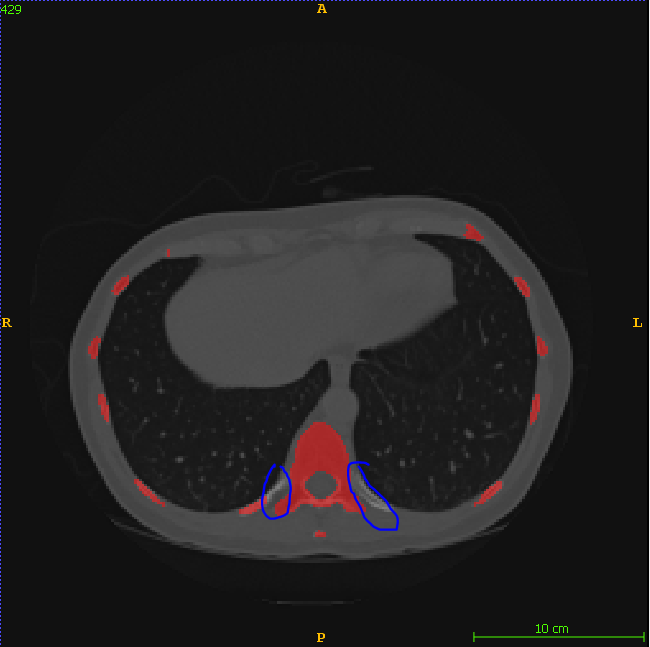

Why is the rib data only partially marked?

Hello, Thank you for all your great work. I found some rib data only partially marked. Was it done on purpose? or just the failed segmentation result? Thanks a lot

The starting point for our rib labels are the segmentations for the ribfracture dataset. Those always excluded the part which is very close to the vertebrae. Therefore this part is always missing.